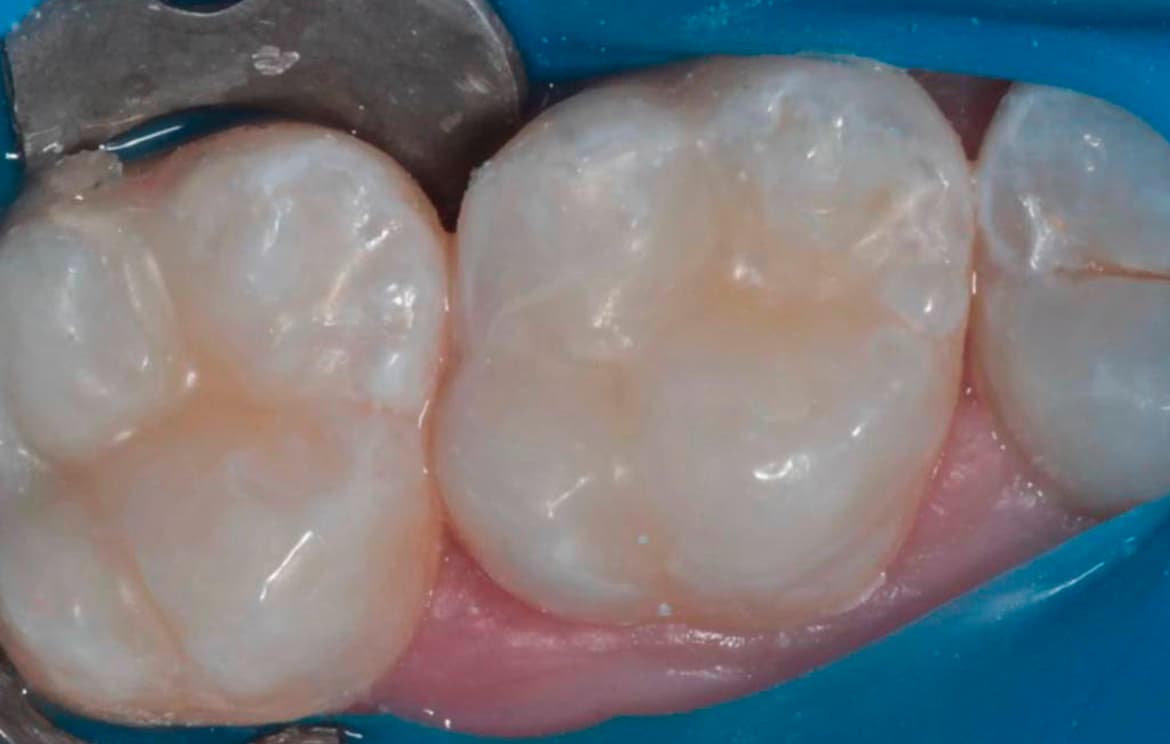

Наши работы